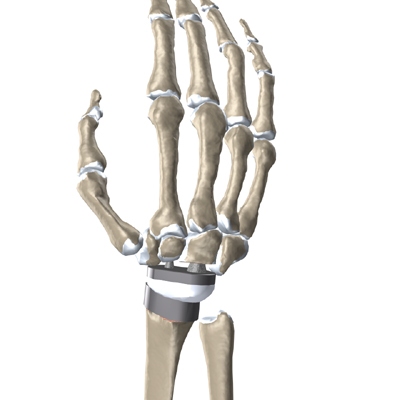

Modern artificial wrist joints are made of metal and plastic. The part that fits against the end of the radius bone of the forearm is called the radial component. It is made up of two pieces. A flat metal piece is placed on the front part of the radius. It has a stem that attaches down into the canal of the bone. A plastic cup fits onto the metal piece, forming a socket for the artificial wrist joint.

The part that replaces the small wrist bones is called the distal component. This piece is made completely of metal. It is globe shaped to fit into the plastic socket on the end of the radius. The metal distal component is attached by two metal stems that fit into the hollow bone marrow cavities of the carpal and metacarpal bones of the hand.

The plastic used in artificial joints is tough and slick. It allows the two pieces of the new joint to glide easily against each other as you move your wrist. The ball and socket allow movement of the wrist in all directions.

Replacement Joint

The surgeon will take some time to get the stems to fit tightly. The joint is put in place and tested through its range of motion to make sure it moves correctly. Once the surgeon is satisfied with the fit, the stems of each metal implant are:

Cemented into Place